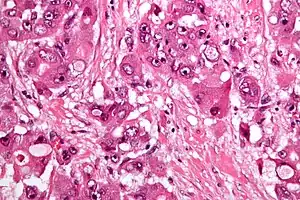

Micrograph of fibrolamellar hepatocarcinoma showing the characteristic laminated fibrosis between the tumor cells with a low NC ratio. H&E stain.

The histopathology of FHCC is characterized by laminated fibrous layers, interspersed between the tumor cells. Cytologically, the tumor cells have a low nuclear to cytoplasmic ratio with abundant eosinophilic cytoplasm. Tumors are non-encapsulated, but well circumscribed, when compared to conventional HCC (which typically has an invasive border).